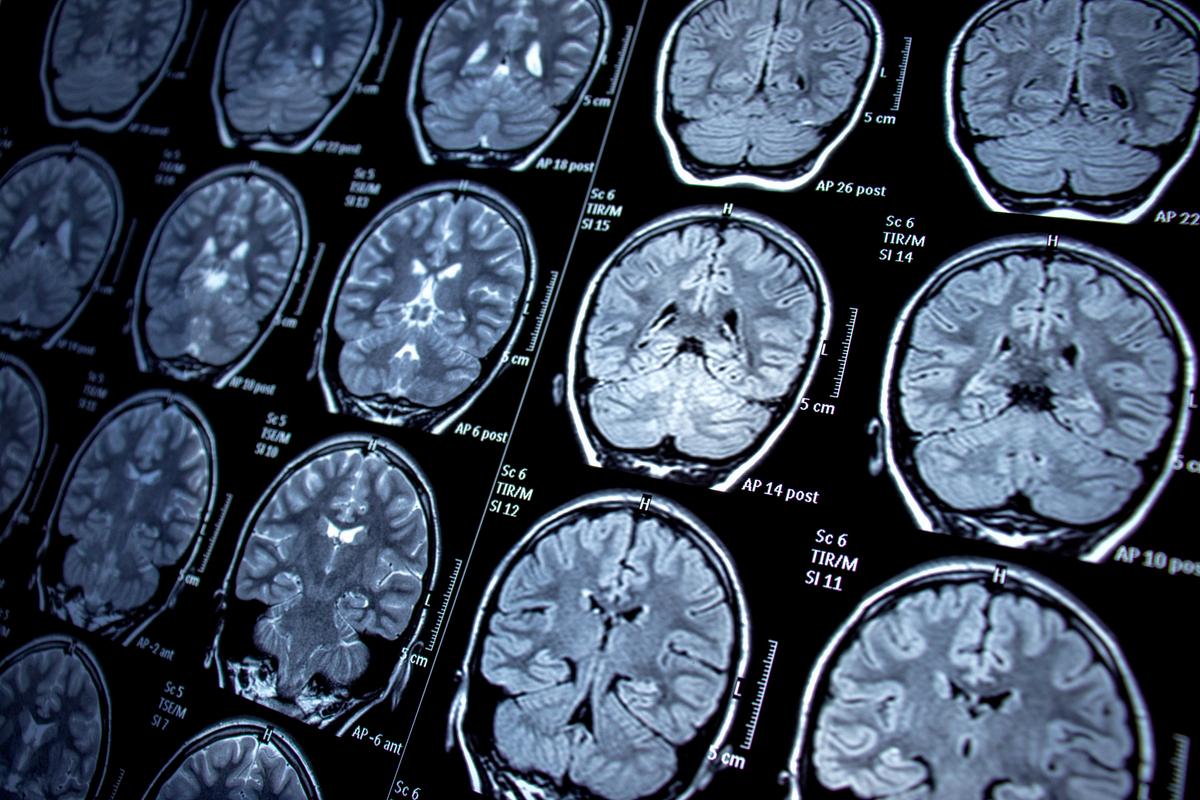

Brain scans

MRI or CT imaging can reveal structural changes, evidence of stroke or tumor, or patterns of atrophy associated with specific dementias.